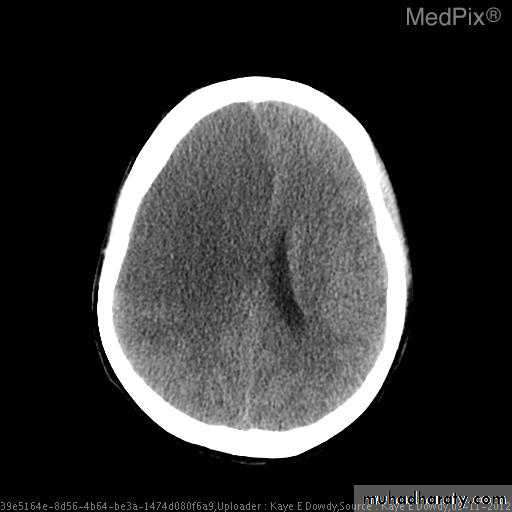

• Haemorrhage is demonstrable on CT immediately after the event as a region of high attenuation

• Frequently causing mass effect.

• The initial high density of haemorrhage lessens over the following week or two leaving a low- density area indistinguishable from an infarct.

• Causes Midline or ventricular displacement.